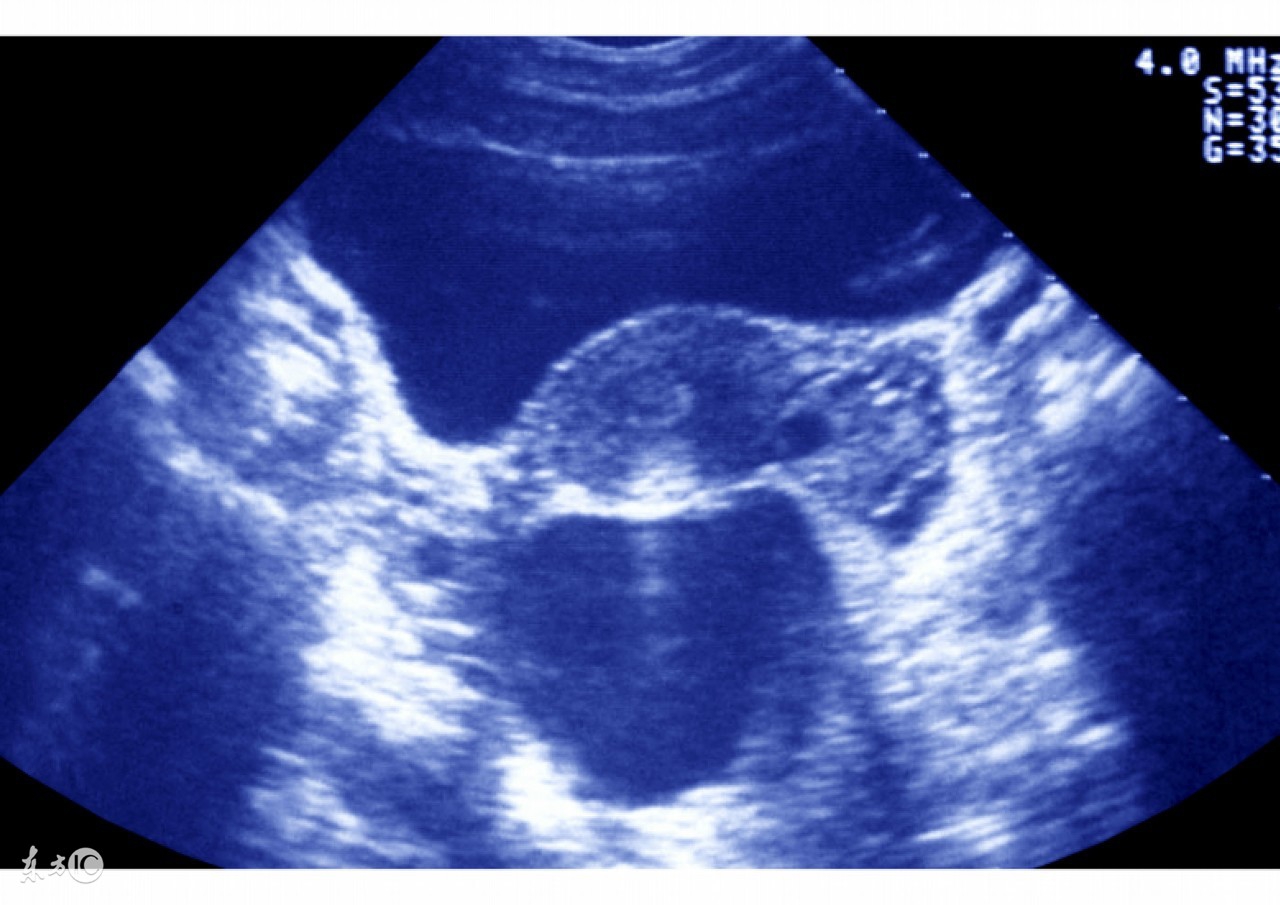

监测排卵时是可以做阴超的,在输卵管腹腔镜切除时应注意:试管婴儿止血要彻底,避免剪除试管婴儿输卵管时,系膜出血或血肿形成;应紧靠试管婴儿输卵管操作,尽量减少对试管婴儿卵巢组织的损伤;若试管婴儿输卵管与周围组织粘连,应先分离试管婴儿粘连,游离试管婴儿输卵管,使其恢复正常解剖后再进行操作,尽量减少对周围试管婴儿组织的破坏。最后检查试管婴儿盆腹腔,用水冲洗,检查有无试管婴儿出血点,排空试管婴儿准妈妈腹腔内气体,取出输卵管腹腔镜,最终缝合伤口。

最后应该强调的是,监测排卵时可以做阴超的,准妈妈不用担心,心情好卵巢环境才会恢复的更快。